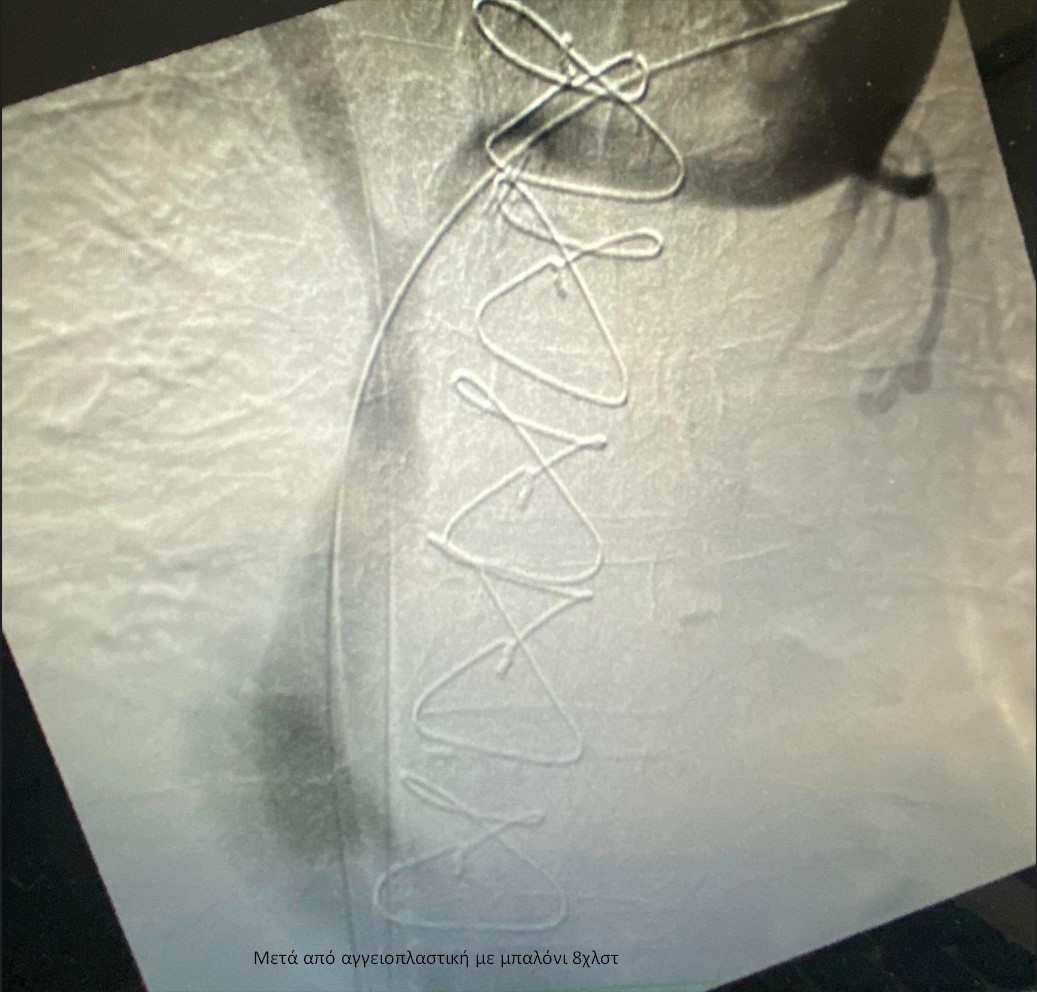

Η ομάδα της Α´ Αγγειοχειρουργικής κλινικής υπό την καθοδήγηση του Διευθυντή Αγγειοχειρουργού Νεκτάριου Γαλάνη και την πολύτιμη συνδρομή του Ακτινολόγου Βασίλειου Δημαρέλου και του Αναισθησιολόγου Δημήτριου Ζωσιμίδη, προχώρησε σε αγγειοπλαστική των πλέον στενωτικών σημείων των ανώνυμων φλεβών και της άνω κοίλης φλέβας υπό ακτινοσκοπική καθοδήγηση. Η προσπέλαση ήταν διπλή με παρακέντηση των μασχαλιαίων φλεβών αμφότερων των άνω άκρων και τοποθέτηση δίδυμων στεντ εύρους 12χλστ και μήκους 80χλστ στη δεξιά και αριστερή ανώνυμη φλέβα και την άνω κοίλη φλέβα, που αποκατέστησαν τη βατότητα των ανωτέρω αγγείων.